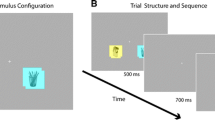

Experimental run

Stimuli for this run consisted of coloured pictures of cigarettes, pencils and chairs in similar colours, presented centrally on a white background. Participants were presented with three runs, consisting of eight blocks of eight pictures of either cigarettes or pencils or chairs. Pictures were presented for 1500 ms with a 50-ms inter-stimulus interval. Stimulus blocks were presented in random order and interchanged with intervals of 10, 12 or 14 s of rest (see Fig. 1). These intervals allowed the blood oxygenated level-dependent (BOLD) response elicited by the previous stimulus block to return back to baseline before the onset of the adjacent block. To ensure attention to the pictures, participants had to respond to catch trials in which presentation of the preceding picture was repeated.